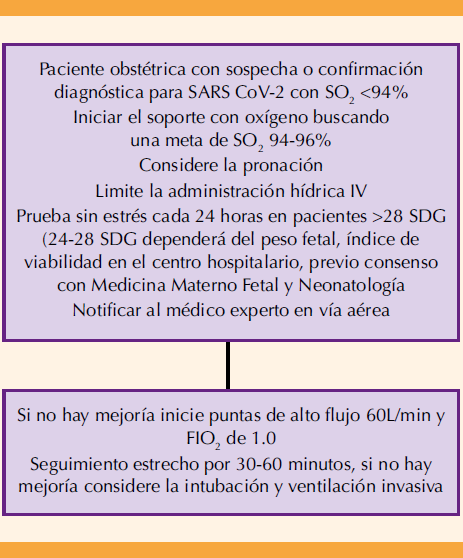

Cuando en la madre se documenta hipoxemia secundaria a infección por COVID-19 está indicado administrar oxígeno complementario a través de los dispositivos de suministro de uso común para dar soporte vital y evitar la fatiga de los músculos respiratorios y mantener metas de presión de oxígeno.71,72 Cuadro 9

Para asegurar una correcta perfusión de oxígeno se recomienda mantener una saturación periférica de oxígeno (SpO2) entre 94 a 98%, además de evitar la hiperoxemia (PaO2 mayor de 120 mmHg) para no contribuir a la generación de radicales superóxido.73

Cánulas nasales de alto flujo

La evidencia actual sugiere que la cánula nasal de alto flujo es superior a la terapia convencional de oxígeno. Las pacientes con indicación para esta terapia de soporte deberán reunir los requisitos indispensables de: estabilidad hemodinámica, estado mental óptimo, reflejo de tos y control adecuado de secreciones. En relación con su efectividad existen algunos reportes de la necesidad de evitar la intubación endotraqueal. Es necesario tomar en cuenta que algunas de esas conclusiones son ambiguas en virtud de que esos estudios pocas veces incluyen a pacientes obstétricas74 pero seguirán siendo útiles en lugares con recursos limitados. En pacientes con deterioro respiratorio nunca debe retrasarse la aplicación de las medidas primarias que puedan evitar la necesidad de llegar, irremediablemente, al soporte mecánico invasivo.71,72,73

Posición prona

La estrategia en decúbito prono despierto es una técnica segura, sencilla y rentable que mejora la oxigenación al incrementar la uniformidad de la ventilación, disminuir la compresión e incrementar el reclutamiento alveolar de la porción dorsal de los pulmones para un mayor intercambio gaseoso, mejorar la distribución de gases hacia la porción ventral y paradiafragmática pulmonar 75,76,77 Esto tiene una repercusión positiva en la oxemia y es factible en pacientes embarazadas o en el puerperio inmediato.78,79 Para colocar correctamente a la paciente se recomienda usar dispositivos de apoyo: almohadas y sábanas alineadas de manera adecuada para evitar la presión excesiva sobre el útero grávido.78 En un estudio retrospectivo, observacional y multicéntrico llevado a cabo en México y Ecuador se concluyó que la posición en decúbito prono de pacientes hospitalizados despiertos, con COVID-19, se asocia con un riesgo menor de intubación y muerte.80

El aspecto más importante de esta maniobra es asegurar que el tubo endotraqueal permanezca en su lugar y proteger las salientes óseas. La posición adecuada del útero gestante permite la monitorización cardiotocográfica fetal.71,72 Si la paciente no muestra mejoría en 10 a 15 minutos habrá deterioro hemodinámico. Si la frecuencia cardiaca fetal no puede monitorizarse de manera satisfactoria deberá suspenderse la pronación.

Las indicaciones para esta posición son: requerimiento de más de 2 L/minuto de oxígeno para mantener una saturación de oxígeno más o menos mayor del 95% o una frecuencia respiratoria mayor de 30 latidos por minuto. Las contraindicaciones absolutas para la pronación son: inestabilidad espinal, fracturas faciales o pélvicas y heridas abiertas de abdomen. Las contraindicaciones relativas son: confusión o incapacidad para cambiar de posición de forma independiente.78